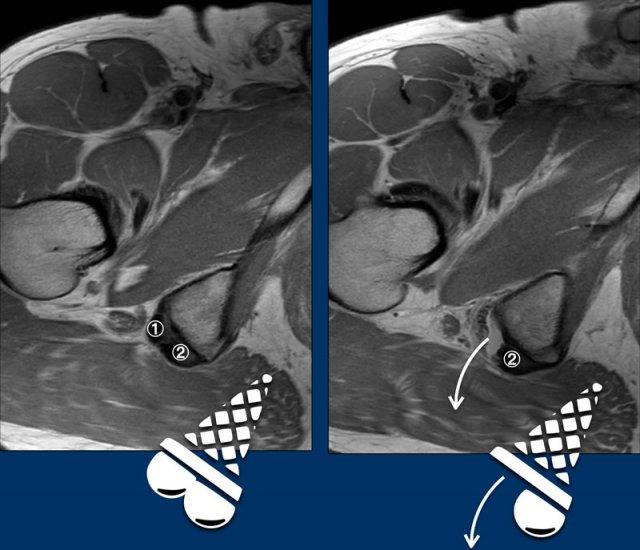

Dấu hiệu kem rơi

Tốt nhất nên xác định gân nào bị rách trên các ảnh axial.

Củ ngồi có thể được hình dung như một chiếc ốc quế kem, với gân cơ bán màng (anterolateral – trước ngoài) và gân chung (posteromedial – sau trong) như hai viên kem với hương vị StracciatelLa CaraMel.

Hình ảnh cho thấy bong gân cơ bán màng.

① Gân cơ bán màng

② Gân chung

Ghi nhớ các hương vị:

Stracciatella – Semimembranosus (cơ bán màng) ngoài

Caramel – Conjoint (gân chung) trong

Ở bệnh nhân này, cả gân cơ bán màng bên phải lẫn gân chung đều bị bong.

Cả hai viên kem đều đã rơi.

Trên các hình ảnh này ghi nhận tổn thương toàn bộ chiều dày.

Cả hai viên kem đều rơi trên ảnh axial, cho thấy cả hai gân đều bị bong.

Trên ảnh coronal, tổng mức độ co rút đã được đo và ghi nhận.